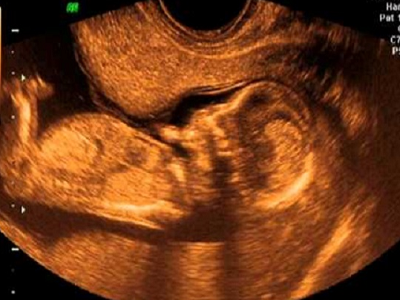

Ultrasonido estructural de 2do. trimestre

Se trata de un estudio visual minucioso y detallado en el cual se evalúan y miden todas las estructuras fetales.